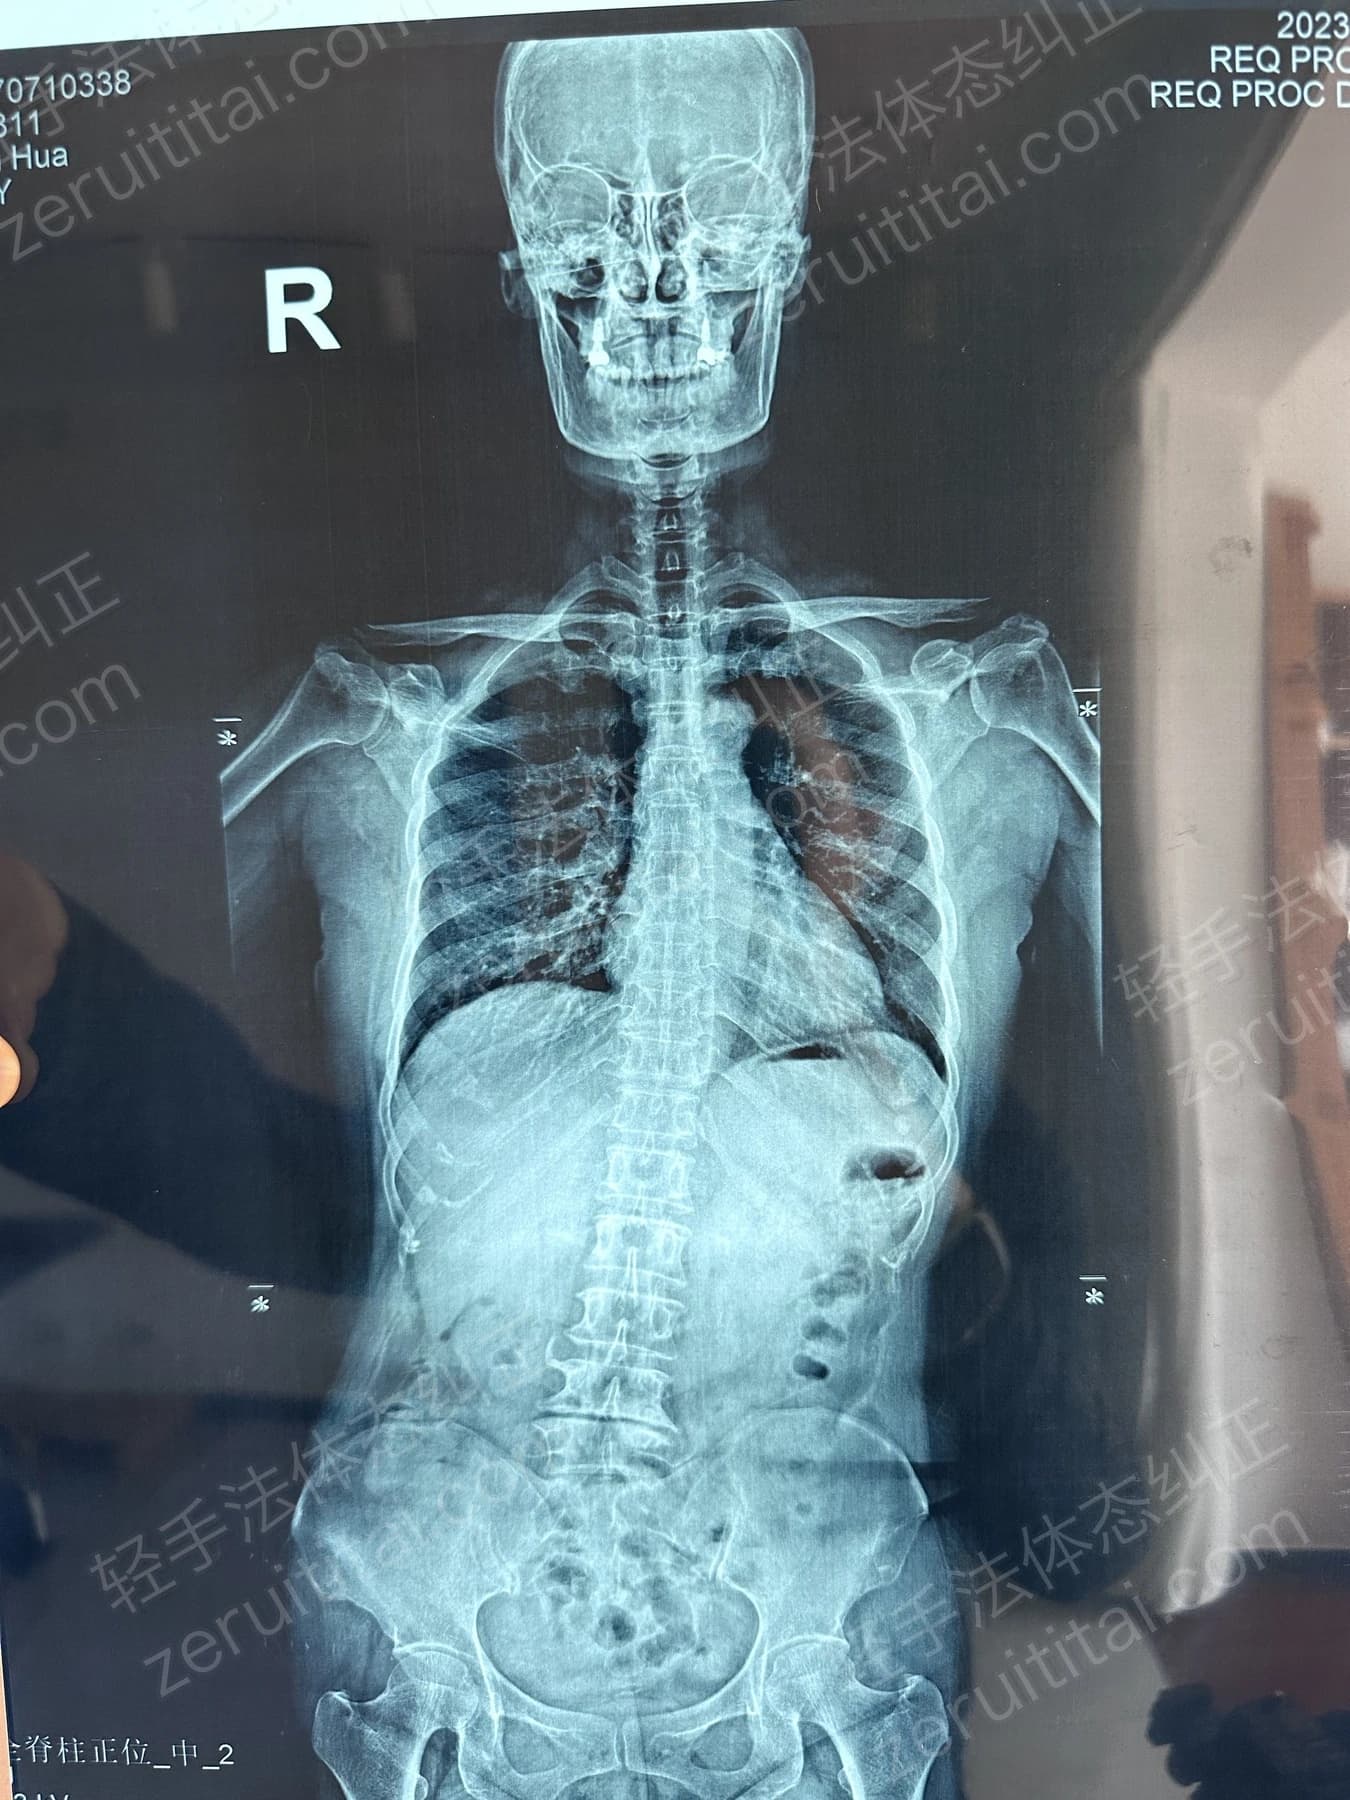

2023.05.30

第 4 次记录